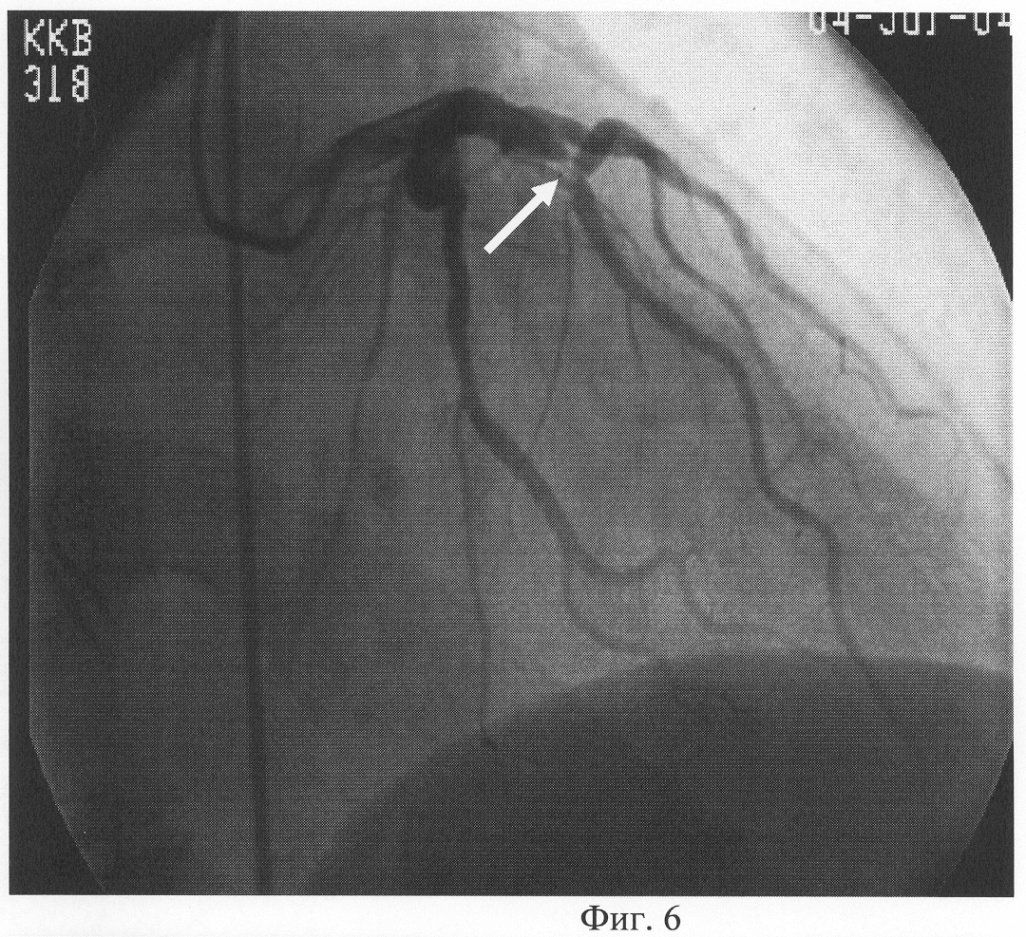

Больной П., 50 лет. Страдает бронхиальной астмой более 10 лет. Поступил в аллергологическое отделение краевой клинической больницы с жалобами на приступы удушья до 6-8 раз в сутки, ночью до 4 раз, купирует беротеком. Одышка при обычной физической нагрузке. Кашель с небольшим количеством вязкой мокроты, слизистого характера. Давящие, загрудинные боли днем до двух раз в сутки в течение 15 минут. При проведении диагностики предлагаемым способом d равен 1,76% (d0=0,56 см, d1=0,57 см). Больному сделана коронарография. На коронарографии сбалансированный тип, гемодинамически значимый стеноз диагональной ветви до 75%. Больному имплантирован коронарный стент («Vision» 3,0×18 мм). После лечения клинические симптомы ИБС не проявлялись. Диагноз при выписке: Бронхиальная астма, эндогенного генеза, тяжелое течение, стероидозависимая, обострение. Сопутствующий диагноз: ИБС, стабильная стенокардия 3 ф. кл. Гиперхолестеринемия 2В типа. Эндопротезирование ДВ («Vision» 3,0×18 мм) 18.06.04. СН I ст. (II ф.к. по NYHA). Гипертоническая болезнь 3 ст., риск 4.

Предлагаемый способ поясняется чертежами, где: на фиг.1 показан ультразвуковой датчик с изображением ОСА; на фиг.2 показан диаметр ОСА у больного ИБС (пример 1) до проведения ингаляции сальбутамолом; на фиг.3 – изменение диаметра ОСА после ингаляции сальбутамолом; на фиг.4 показан диаметр ОСА у пациента (пример 2) до проведения ингаляции сальбутамолом; на фиг.5 – изменение диаметра ОСА после ингаляции сальбутамолом; на фиг.6 приведена коронарограмма больного ИБС (пример 1); на фиг.7 – коронарограмма пациента (пример 2).